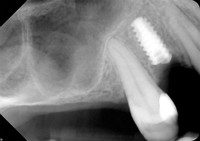

Poor quality implant placed in Argentina, which subsequently broke in half. Patient had treatment remedied here at Dental Artistry.